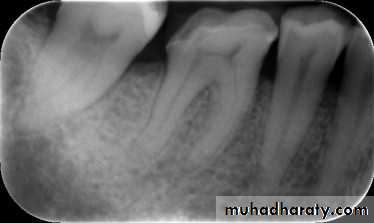

Typically, there are minimal or no changes in the radiographic appearance of the periradicular bone.With advanced irreversible pulpitis, a thickening of the periodontal ligament may become apparent on the radiograph, and there may be some evidence of pulpal irritation by virtue of extensive pulp chamber or root canal space calcification or even internal resorption

Deep restorations, caries, pulp exposure, or any other direct or indirect insult to the pulp, recently or historically, may be present

This is a clinical diagnosis based on subjective and objective findings indicating that the vital inflamed pulp is incapable of healing. The patient, however, does not complain of any symptoms. On occasion, deep caries will not produce any symptoms, even though clinically or radiographically the caries may extend well into the pulp.Left untreated, the tooth may become symptomatic or the pulp will become necrotic. In cases of asymptomatic irreversible pulpitis, endodontic treatment should be performed as soon as possible so that symptomatic irreversible pulpitis or necrosis does not develop and cause the patient severe pain and distress